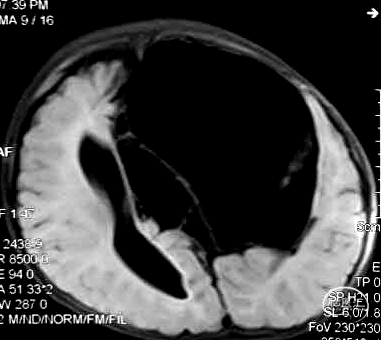

男,5周,囊肿-腹腔分流术

3个月后